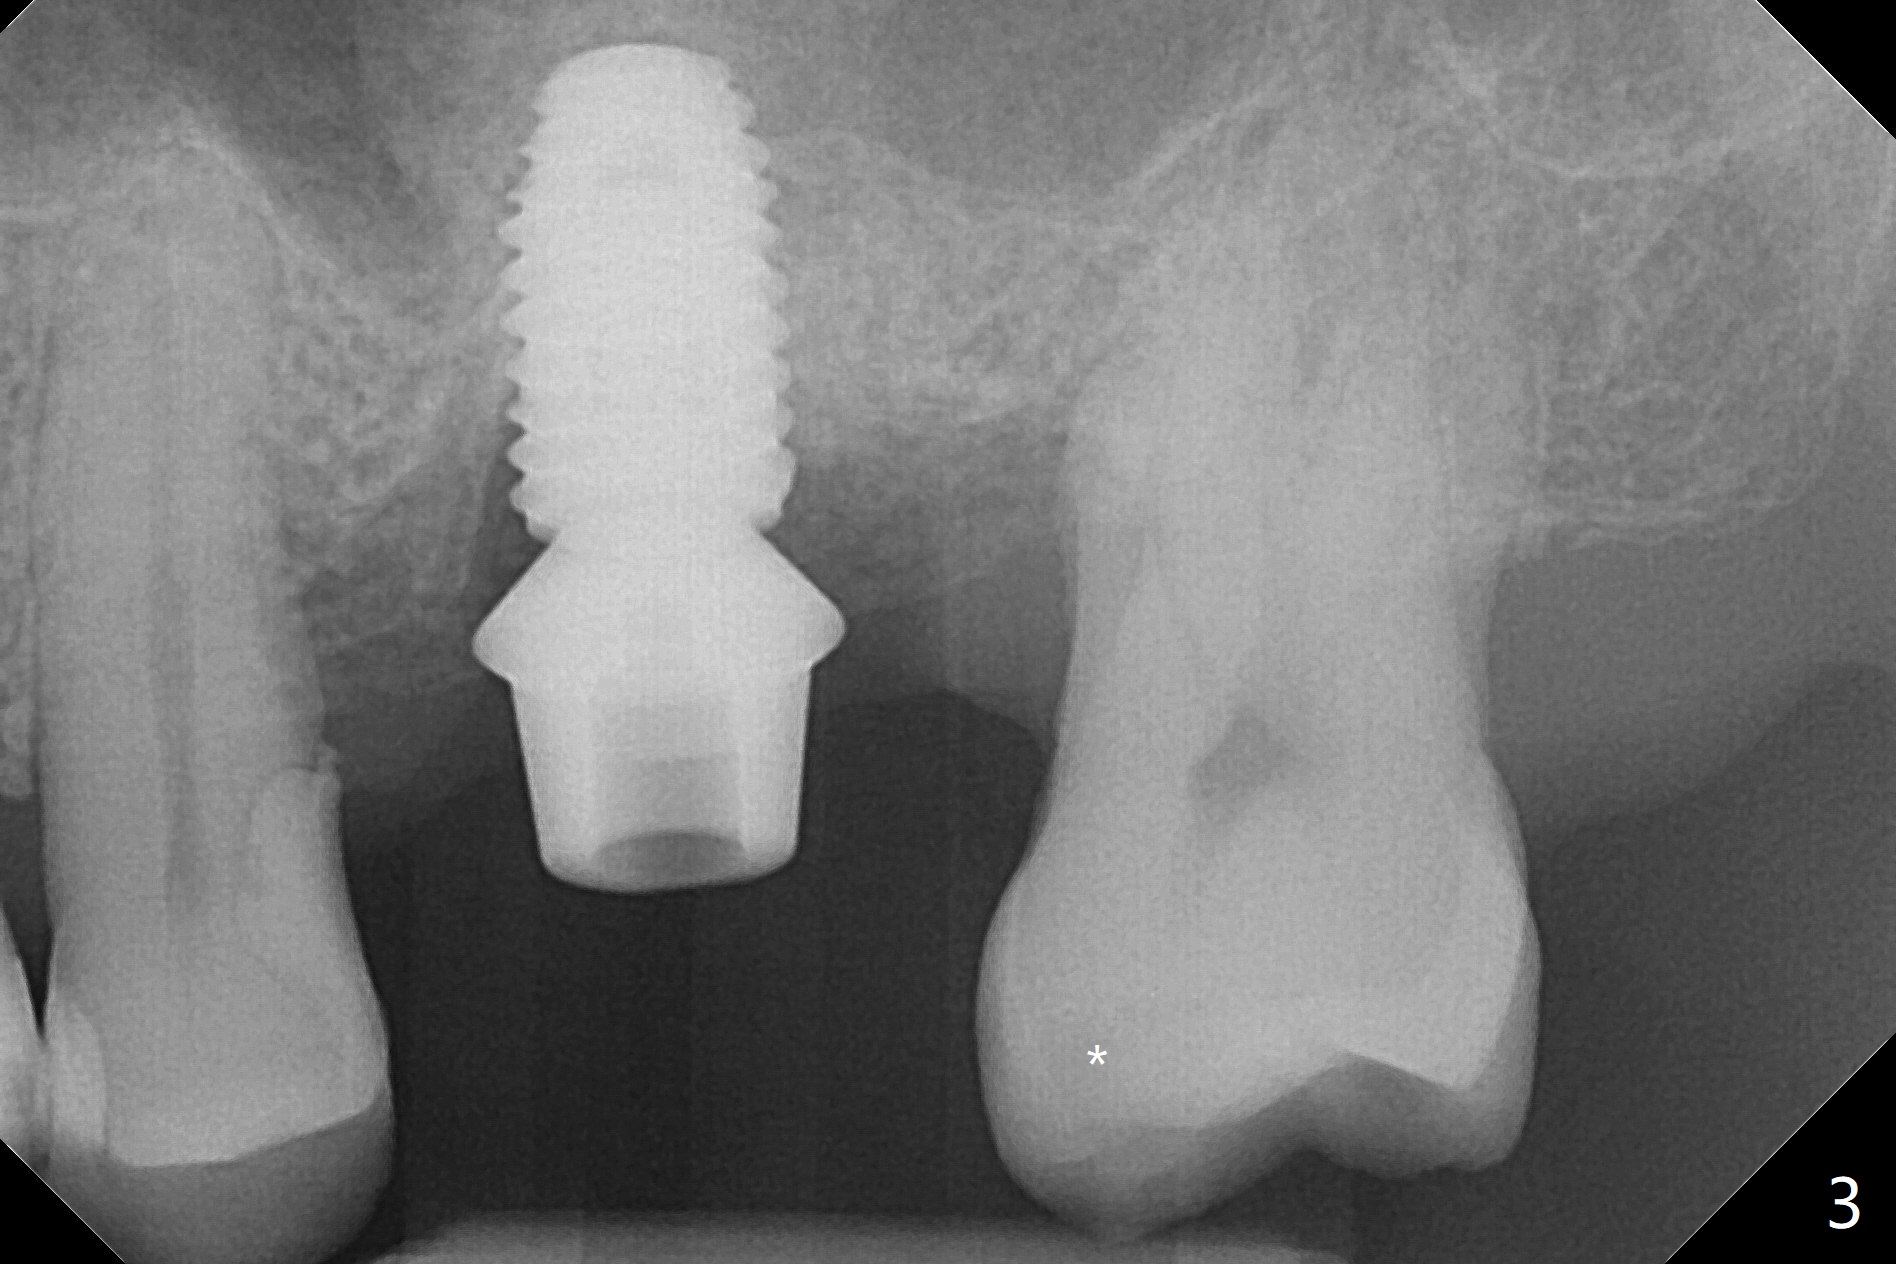

72岁男4.5前左上第二磨牙位置正常(图一),当时左下第二磨牙龋齿严重(图二),后来在别的诊所拔除,最近回来要求左上第一磨牙(图三)和左下第二磨牙种植(图四),由于左上第二磨牙延申(图五),为了左下第二磨牙导板种植,左上第二磨牙近中舌侧牙尖必须磨除不少(图三:*),总之,第二磨牙导板延期种植吃力,下午第二磨牙导板即种就没有这方面困难。